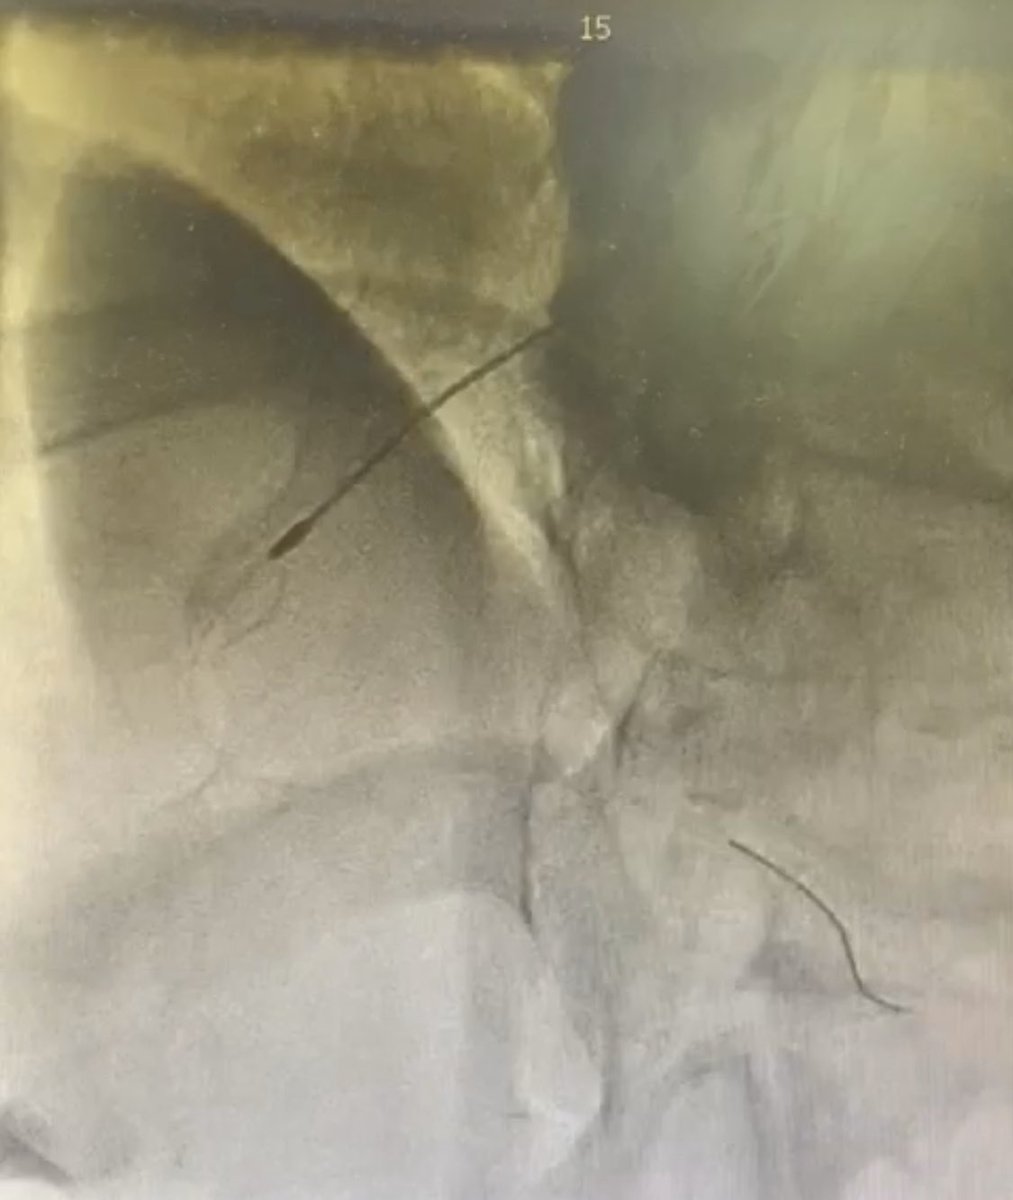

After considering making an early transition to industry but struggling to walk away from the lab, damn it feels good to get the #CHIP train rolling again! 1st #PercAx LM #rotapro in NJ & single #safefemoral access with 7fr dest via CP. Off-label but 💯! Props to @jason_wollmuth

RajTayalMD's tweet image. After considering making an early transition to industry but struggling to walk away from the lab, damn it feels good to get the #CHIP train rolling again! 1st #PercAx LM #rotapro in NJ & single #safefemoral access with 7fr dest via CP. Off-label but 💯! Props to @jason_wollmuth